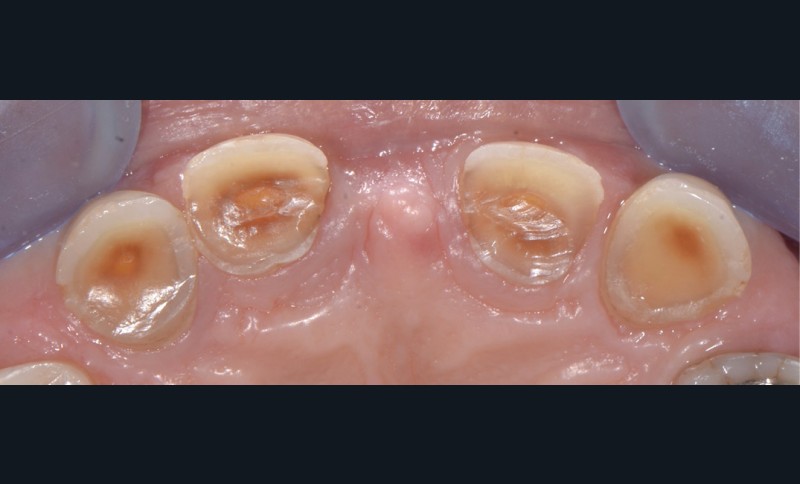

Prenons les lésions cervicales non carieuses, exemple typique de zone de dentine sclérotique (fig. 3) :